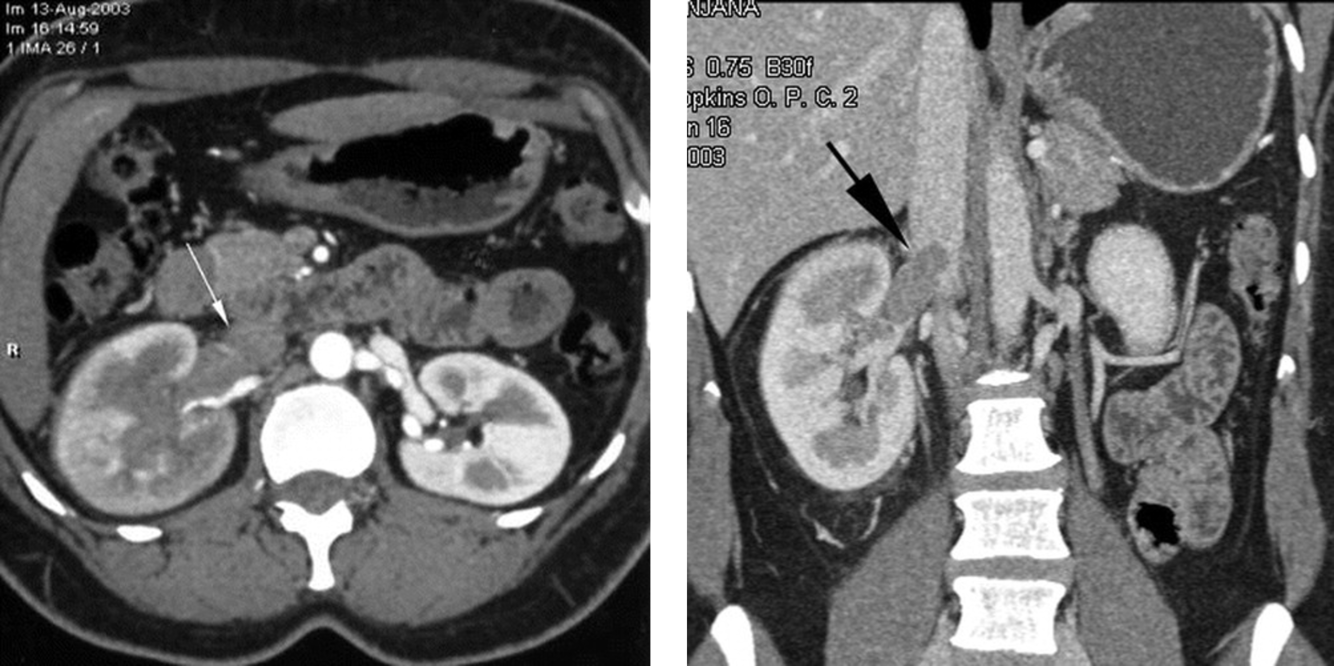

fever and leukocytosis

pyelonephritis with right renal vein thrombus